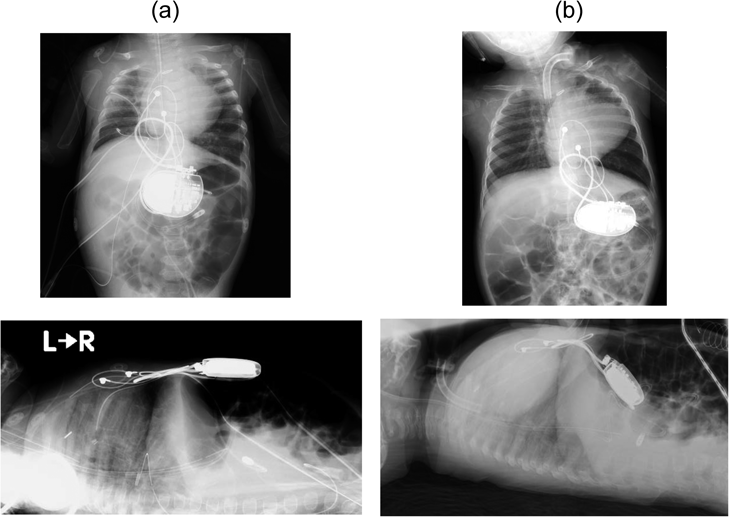

Fig. 1 PMI後の胸腹部単純X線写真

(a) 植込み直後(5か月時),(b) 診断時(1歳2か月).

Double outlet right ventricle(DORV)の胎児診断ののち,在胎31週6日,体重は1,239 gで出生した.出生後subpulmonary ventricular septal defect(VSD)を伴うDORV, Coarctation of the Aorta(CoA)の診断となった.生後4日に肺動脈絞扼術を行ったのち,生後3か月時にArterial Switch Operation・VSD closure・CoA repairを行った.術後は誘引なく洞徐脈および完全房室ブロックが出現し循環不全を繰り返した.徐脈時には術後留置していたtemporaryリードからAAIペーシングを試みたが有効なpacingができなかった.心停止も経験し,二度の体外式膜型人工肺管理を要した.冠動脈はShaher 9型で,右冠動脈孔は非常に小さな2つの開口部に分かれており,開口部異常・起始部狭窄と診断した.これに伴うsinus node dysfunctionが一過性徐脈の原因と考えられたが,冠動脈起始部への介入は技術的に困難であったため,PMIの方針となった.術後2か月(生後5か月)時,体重4.3 kgで心外膜リードを用いたPMI(Generator: Medtronic社Attesta ATSR01,心室リード:Medtronic社CapSure Epiを使用し,single chamber pacing, bipolar pacing)を行った.徐脈時に房室ブロックを伴うためVVI(lower rate 90 bpm)で設定した.機種は自施設で選択できる機種の中で容積が最小のものを選択した.generatorは左上腹部腹壁の腹直筋筋層直下・腹膜上に植込まれた.前述の右冠動脈起始部狭窄および肺動脈分岐部狭窄に伴う両心室機能低下のため,人工呼吸器管理からの離脱に難渋し,7か月時に気管切開術を行い,以降は人工呼吸器管理を継続している.慢性心不全のため栄養が進まず,体重は4か月時に3.0 kg台に到達,1歳時は4.6 kgと顕著な体重増加不良がみられた.また,運動発達遅滞がみられ,1歳時点で寝返りができず入院管理中は仰臥位での長期臥床状態であった.PMI後インピーダンスや刺激閾値の変化はみられていなかったが,1歳2か月時,generatorを皮下直下に触れずgeneratorのmigrationを疑い,胸腹部レントゲン撮影を行った.正面像ではgeneratorの傾きの変化を認め,側面像では背側へのmigration,腹腔内migrationを認めた(Fig. 1).migrationと診断された時点ではgenerator migrationによる重篤な合併症(腸閉塞や腸管穿孔などの消化器病変)は認めていなかったが,その後に生じる危険性を踏まえ,治療介入が必要と判断した.ただし,植込み術から9か月が経過しており既にgenerator周囲はポケットを形成し,さらにレントゲンではリードのたわみもあまり変化ないことから,generatorが腹腔内でさらに背側や尾側へmigrationが進展する可能性は低いと考え,抜去術までの時間の猶予があると判断し,緊急抜去術は行わなかった.一方で,徐脈を呈しpacingを要する頻度は減少し,PMIから4か月後(生後9か月)以降はほぼpacingを要さず,migration診断時点で数か月間pacingされていない状態であった.いったん退院し,自宅生活でもpacingが不要であることを確認する期間を設けてgeneratorの留置継続は不要と判断し,migrationの診断から6か月後の1歳8か月時にgenerator抜去術を行った.

migrationの診断には触診やレントゲン撮影が有用である.触診時に皮膚直下にgeneratorを触れないことでmigrationを疑うことが可能である.疑った際にはレントゲン側面像の撮影にて容易に診断ができる.なお,本症例においては正面像でのgeneratorの角度異常からもmigrationを疑うことが可能であった.